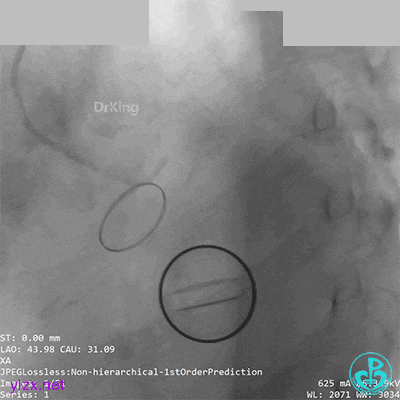

05 急诊冠脉造影

前降支血流3级,前降支近段、对角支开口大量血栓,回旋支开口闭塞。